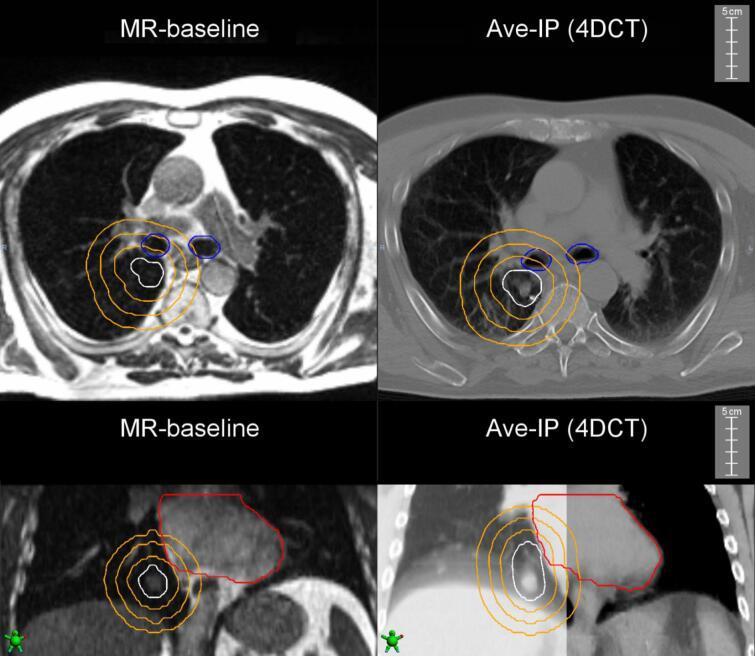

Higher toxicity rates are associated with stereotactic ablative radiotherapy (SABR) to central lung tumors. Breath-hold (BH) magnetic resonance-guided SABR (MR-SABR) can reduce doses to organs at risk (OAR). We quantified the planning target volumes (PTV) to OAR distance in 45 lesions treated using MR-SABR and generated a corresponding four-dimensional computed tomography (4D-CT) based PTV (motion-encompassing internal target volume plus 5 mm). For lesions located ≦3 cm from airways, BH MR-SABR increased the median PTV distance to OAR by 3.7 mm. For lesions ≦3 cm from pericardium, median PTV-OAR separation increased by 2.0 mm with BH. These findings highlight the advantage of BH SABR for central lung tumors.

摘要

较高的毒性发生率与立体定向消融放疗(SABR)治疗中央型肺肿瘤有关。屏气(BH)磁共振引导下的SABR(MR-SABR)可减少对危及器官(OAR)的剂量。我们对45个采用MR-SABR治疗的病灶的计划靶区(PTV)到OAR的距离进行了量化,并生成了相应的基于四维计算机断层扫描(4D-CT)的PTV(包含运动的内部靶区体积加5毫米)。对于距离气道≤3厘米的病灶,BH MR-SABR使PTV到OAR的中位距离增加了3.7毫米。对于距离心包≤3厘米的病灶,BH使PTV与OAR的中位间距增加了2.0毫米。这些发现突出了BH SABR治疗中央型肺肿瘤的优势。